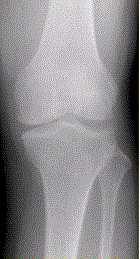

问题 患者女,54岁,右膝关节痛。实验室检查:类风湿因子阳性,除外膝关节类风湿性关节炎。X线检查结果如下图。 观察X线平片后,最可能的诊断是

选项 A.膝关节退行性骨关节炎 B.膝关节类风湿性关节炎 C.膝关节色素沉着绒毛结节性滑膜炎 D.膝关节滑膜型结核 E.血清阴性脊椎关节炎膝关节侵犯

答案 A